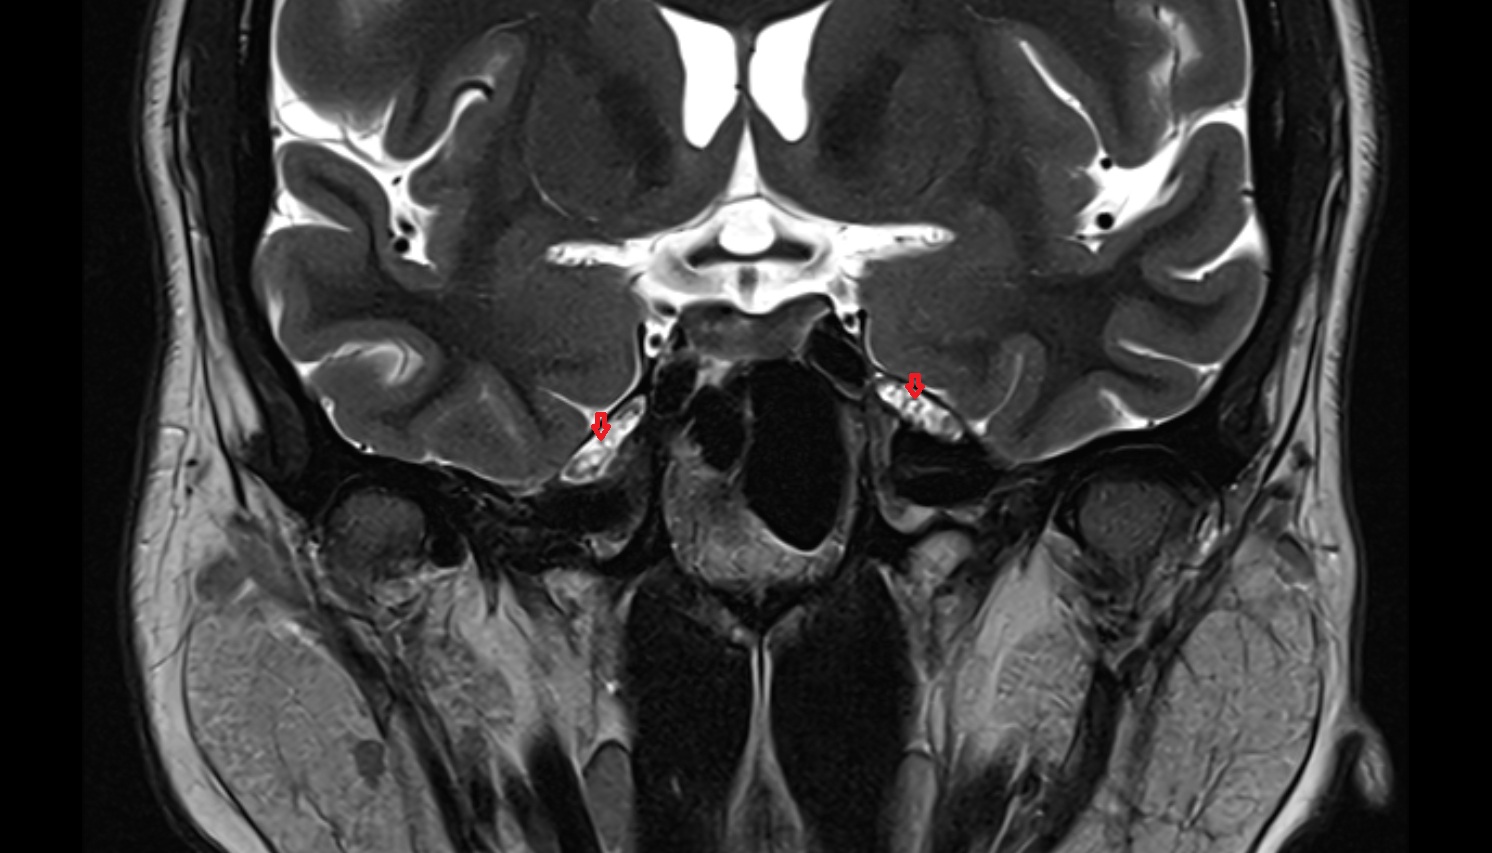

Meckel’s cave (Trigeminal cave) mri coronal image -img-00000-00000

T2-weighted images:

• The cave is hyperintense due to CSF, creating a bright background that clearly outlines the ganglion.

• Nerve fibers and lesions may be distinguished by intermediate or heterogeneous signal intensity.

• Useful for detecting edema, cysts, or tumors involving the trigeminal nerve or ganglion.